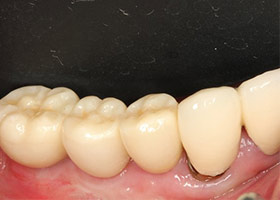

![proimages/case/Artificial_implant/HON08-2.jpg proimages/case/Artificial_implant/HON08-2.jpg]()

14.病患恢復正常咬合功能。